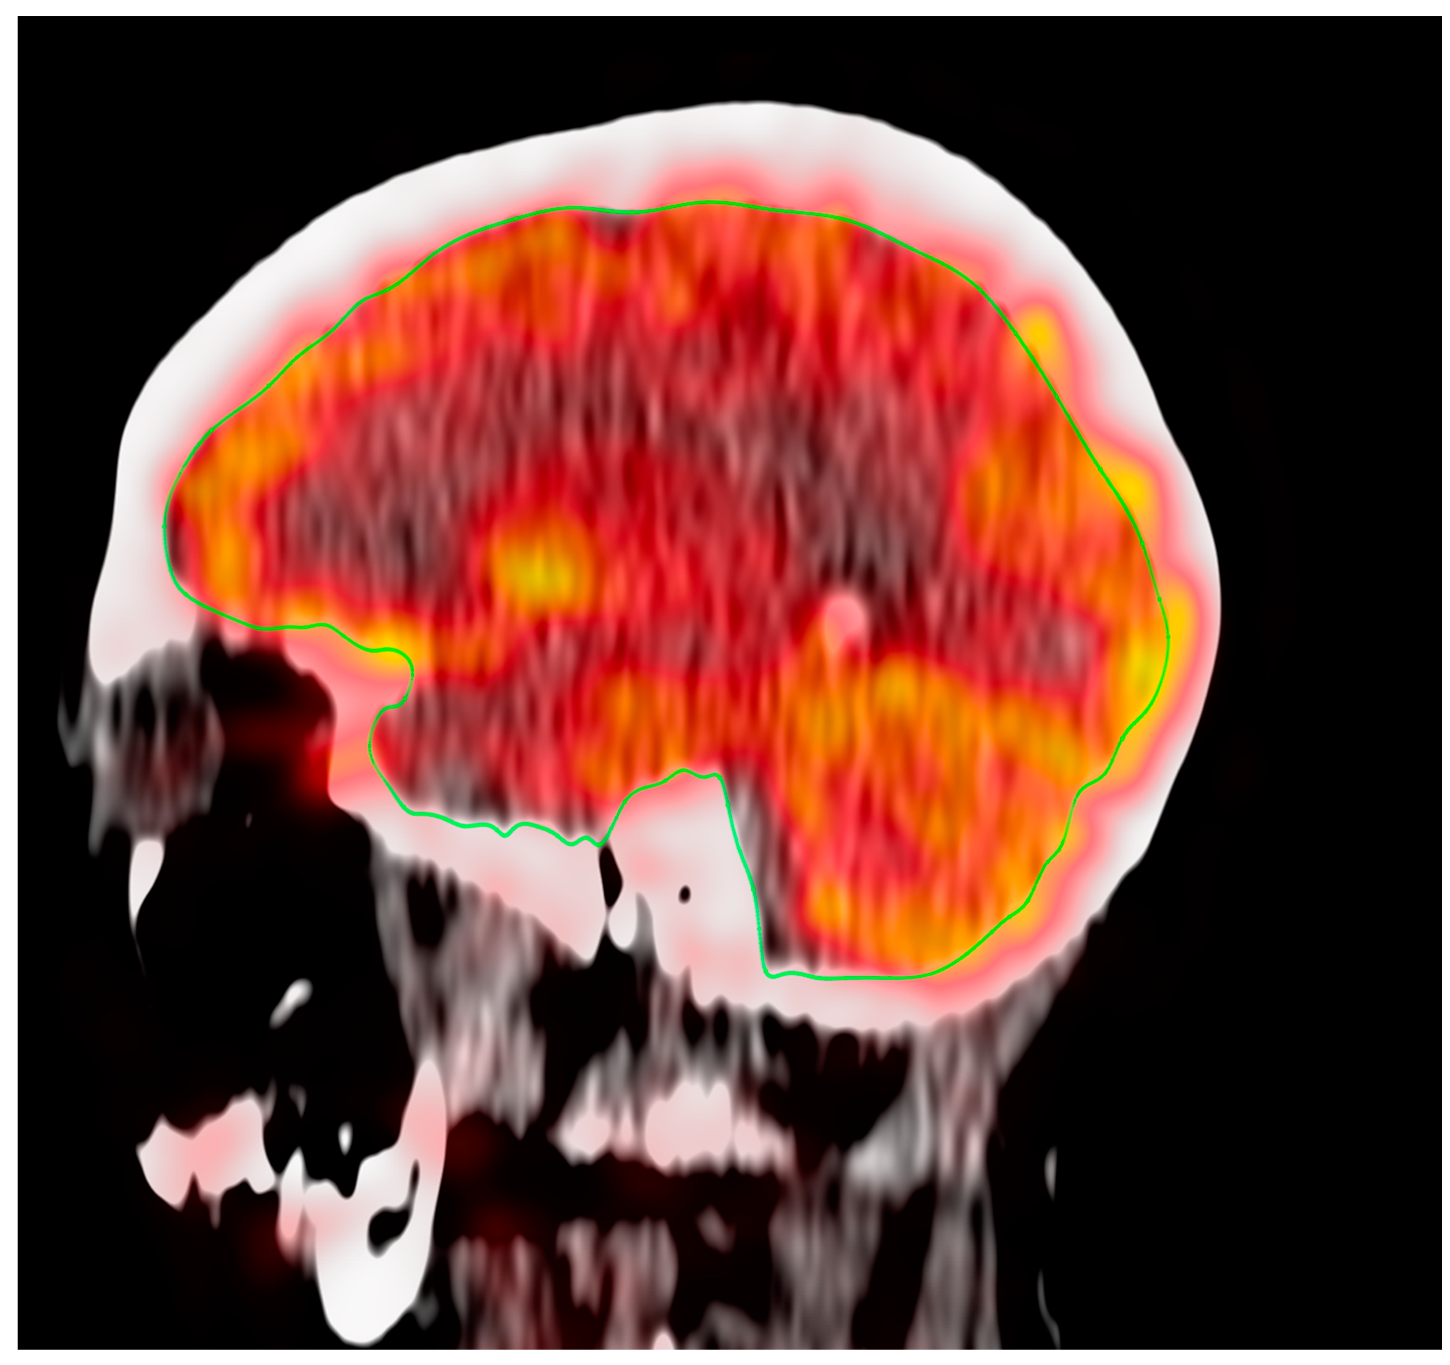

3.2. Effect of Aging on Global Cerebral Metabolic Activity

3.3. Effect of Aging on Regional Cerebral Metabolic Activity